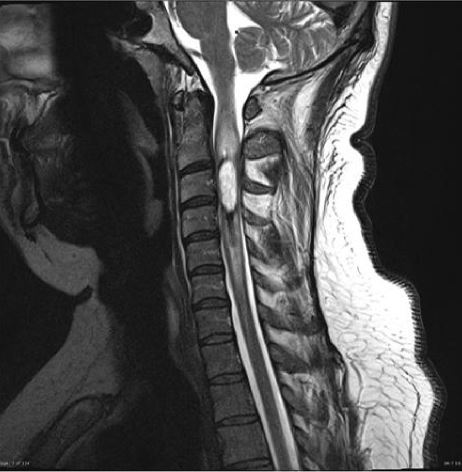

17

Q

-modality -weight -orientation -body part -contrast -abnormality

A

-MRI -T2 -saggital -cervical spine -can’t tell with T2 -intramedullary cervical cord tumor